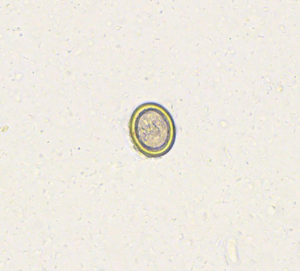

Giardien

Befallen: Hunde und Katzen jeden Alters

Mögliche Symptome: Durchfall (besonders bei Welpen und Kitten)

Zoonose: Obwohl es selten ist, ist eine Infektion möglich